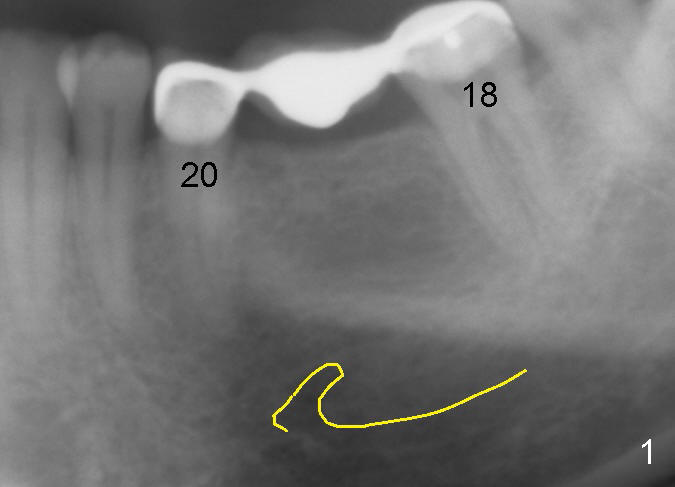

A 47-year-old man has lost a lower left fixed partial denture (FPD) for a while (Fig.1,2).  There is limited space between the abutments (of the teeth #18 and 20) and the opposing dentition.  The edentulous ridge is wide enough to use a 4 mm tissue punch.  A 5.3x14 mm bone-level implant is to be placed (Fig.2).  The base of the implant is at the level of the apices of the neighboring teeth.  As compared to Fig.1 in term of the Inferior Alveolar Canal (yellow line), there should be enough safe margin.  The first intraop PA is taken after 2 mm pilot drill for depth and trajectory check,  Drill stops are to be used for safety.  If primary stability is achieved, an abutment is placed and a provisional bridge will be fabricated to prevent further narrowing of the interocclusal clearance during 3-4 months of osteointegration.  How is outcome?